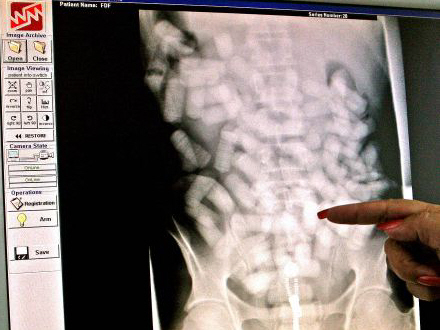

De sluger fra 500 gram og op til et kilo narko, mens én mand er taget med hele 1,233 kilo narko i organerne. Typisk smugles kokain, men også heroin finder vej til danske misbrugere i smuglernes maver.

Det er tydeligt at se poserne med narko på scanningsbilleder